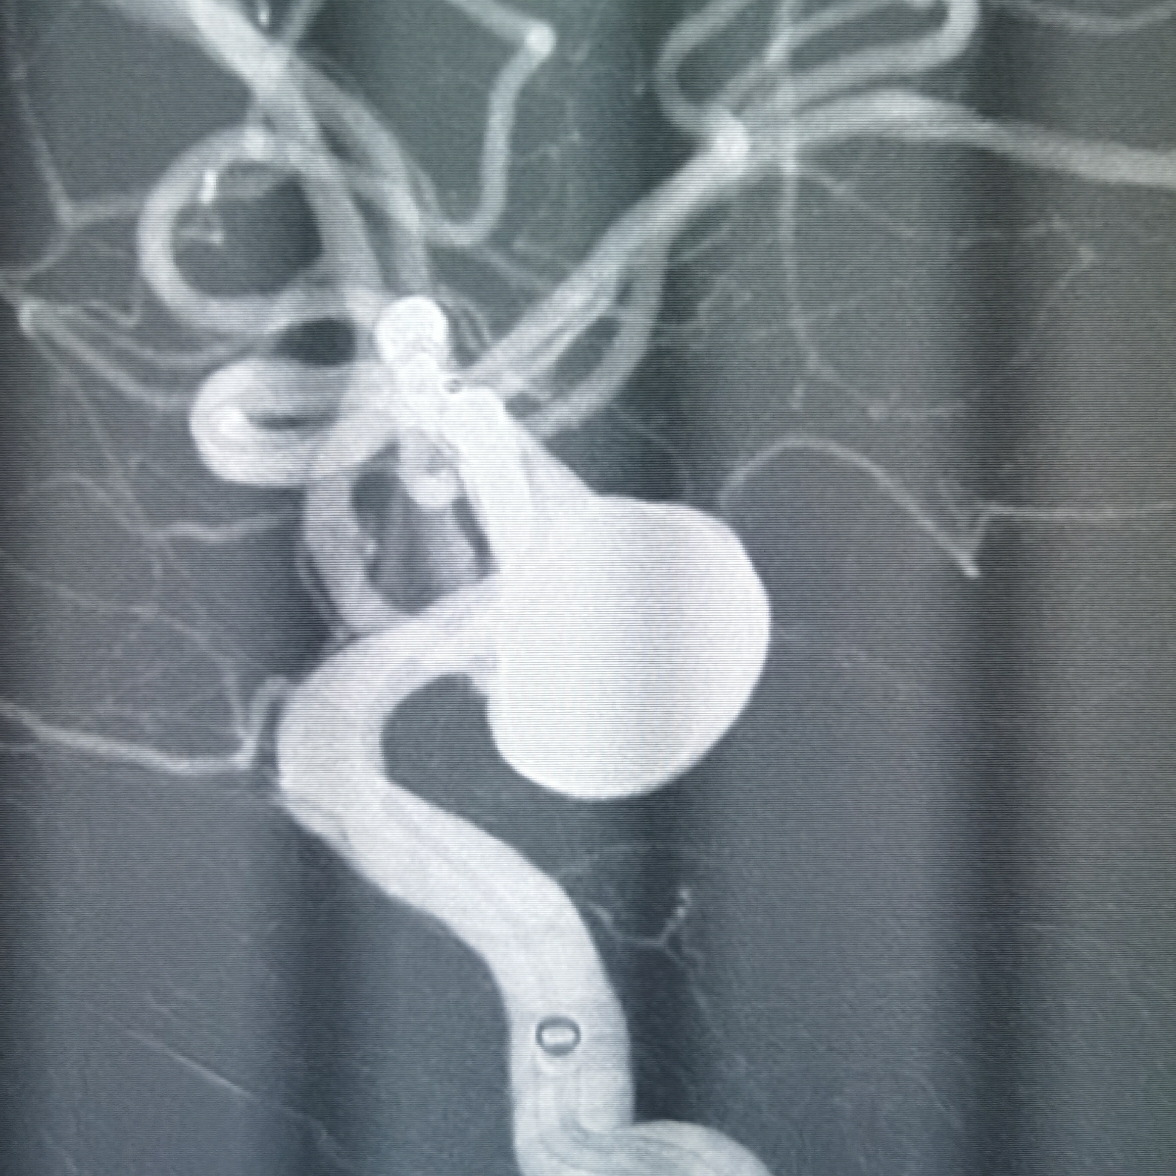

CTA可见左侧颈内动脉颅内段巨大动脉瘤,瘤体12.5*14*9mm。

左侧颈内动脉C7动脉瘤改变。